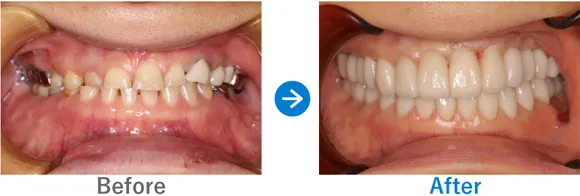

Case5

ほぼ虫歯な状態から、できるだけ歯を残した最小限のインプラントできれいな口元に

全顎ランパントカリエス(複数の歯に同時に虫歯が発生する状態)

インプラント4本:上顎2本、下顎2本、残せる歯はすべて補綴治療

4,917,000円(内訳:抜歯テルプラグ、GBR、根管治療、インプラント4本(ストローマン)、ガイド、全顎仮歯、補綴治療、セデーション、保証20年)

来院の背景

歯医者が苦手で、子供時代に歯科にかかったきりでした。ほとんどの歯に虫歯がある状態だったため、心配になったお父様が連れてこられました。

治療結果

まだお若いため、残せる歯はできるだけ残したうえで補綴治療(クラウンやブリッジなどによる治療)を行い、どうしても抜歯が必要な歯4本のみインプラントを行う方針で治療を進めました。

治療後は、見た目が整ったことはもちろん、しっかり噛めるようになったと喜んでいらっしゃいました。歯磨きが苦手とのことなので、定期メンテナンスでのアフターフォローも大切です。